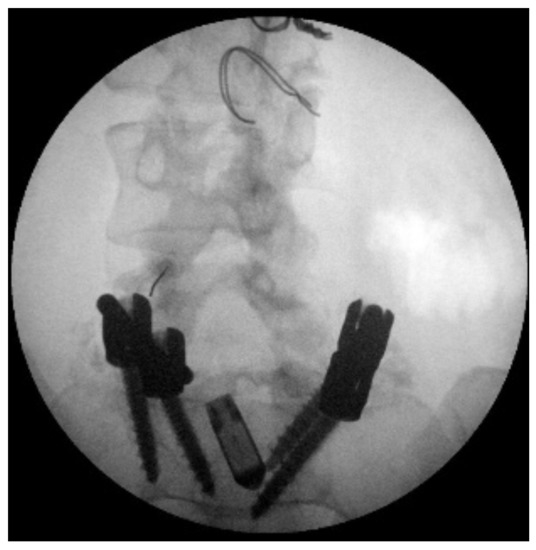

- -